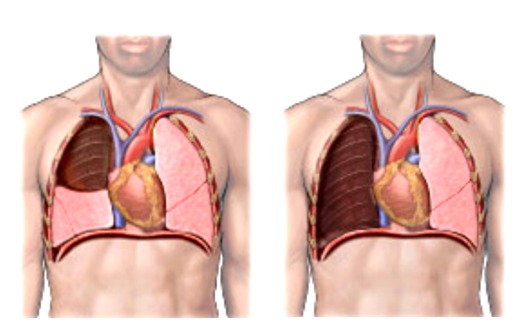

- по объему резекции (лобэктомии (удаление доли легкого), билобэктомии (удаление двух долей легкого), пневмонэктомии (удаление целого легкого)),

Фото 3 — Лобэктомия и Фото 4 — Пневмонэктомия